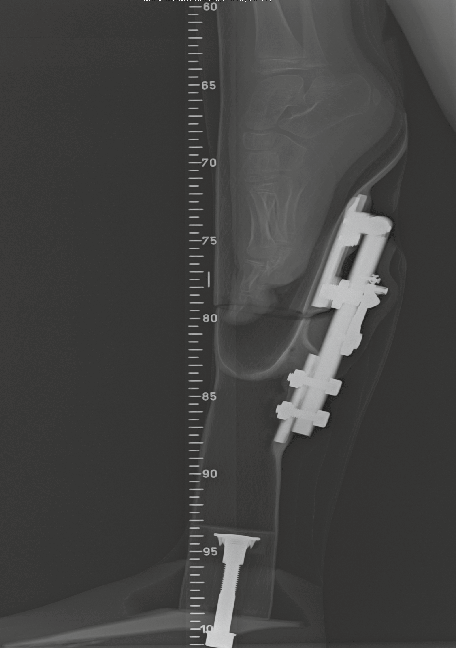

Es wurde ein Alu-Gelenk konstruiert, das flach genug ist, um hinter dem Kinderfuß Platz zu finden (Abb. 3). Der Pin der Sperre besteht aus gehärtetem Stahl. Er ist in einem Feingewinde mit einer Gegenmutter aus Messing befestigt. Dies erlaubt eine feine Regulierung und erhöht die Passgenauigkeit. Der Sperrhammer bewegt sich auf lateralen Druck; die Rückführung der Sperre wird mittels einer Feder erreicht.

Für den Aufbau wird die Prothese steif anprobiert. Das Gelenk wird auf Schaft und Balsaholzteil befestigt; dabei muss auf die Stellung geachtet werden, so dass die sitzende Position ermöglicht wird. Erst dann sägen wir die Prothese auf Zehenhöhe ab (damit diese in sitzender Position ebenfalls frei liegen). Somit erreichen wir eine minimale Länge des proximalen Segmentes (Abb. 4 u. 5). Sobald die Größe des Kindes es zulässt, wird unser selbst entwickeltes Knie durch ein hydraulisches Einachs-Kniegelenk ersetzt. Das erzielte Resultat im Erwachsenenalter spricht gegen eine Amputation des Kinderfußes.